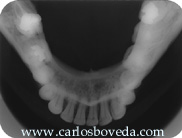

Nos

llamó la atención la imagen

radiopaca que se evidencia periapical al

primer molar. En el momento analizamos con

detalle su examen radiográfico

periapical completo e indicamos la toma de

una radiografía panorámica

dental-sinusal.

Este

examen radiográfico

periapical se encuentra

digitalizado en dos segmentos. El

primero contiene la zona

posterior derecha y el segundo

contiene la zona anterior y la

zona posterior izquierda. Haga

click sobre el segmento de la

imagen que desee agrandar. La

radiografía

panorámica fue tomada

posterior al tratamiento

endodóntico del tercer

molar inferior derecho. Haga

click sobre ella si la desea ver

a mayor

resolución.

La

historia clínica de la paciente no

aporta ningún dato de

significancia. De igual manera no se

refiere de sintomatología alguna.

Las evaluaciones radiográficas

evidencian la unilateralidad de la imagen

radiopaca periapical a la raíz

distal del primer molar inferior derecho.

Clínicamente no se evidencia

crecimiento alguno del maxilar en esa

área. La palpación de la

zona o la percusión de los dientes

cercanos no produce respuestas positivas.

A excepción del tercer molar que ya

fue tratado endodónticamente, todos

los dientes del maxilar inferior en su

lado derecho responden positivamente a las

pruebas de vitalidad, dentro de

parámetros de normalidad. Las

imágenes radiográficas

sugieren una disminución del

espacio pulpar del primer molar inferior

derecho, así como una posible

alteración de la arquitectura

apical en su raíz

distal.